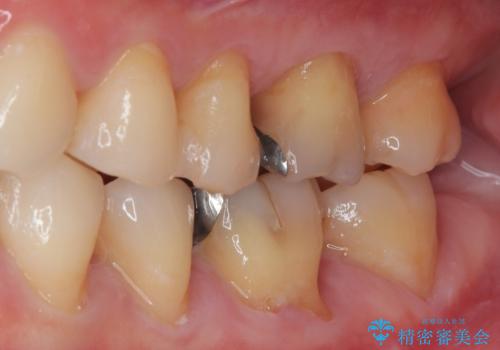

特に異常もなく見た目、噛み合わせともに満足していただけました。

ラバーダム防湿を行い、セラミックの接着をすることで、唾液や血液などの接着阻害因子を排除することができます。

歯と歯の間の虫歯をコンポジットレジンや保険のメタルインレーで治すと段差ができたりして清掃性が悪くなるので、セラミックインレー修復やゴールドインレー修復などの適合の良い詰め物で治療することをオススメします。